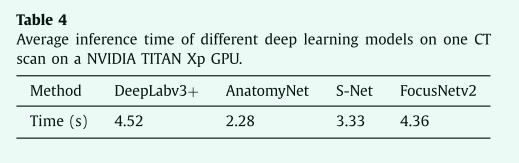

表3 Dice score coefficient (%) 与之前在 MICCAI2015 数据集上公布的结果比较,灰色的列是小器官。

Experiments on MICCAI’15 dataset

Comparison with state-of-the-arts

我们还在MICCAI 2015头颈数据集上测试FocusNetv2。FocusNetv2的所有设置与我们收集的数据集上的实验中使用的设置相同,只是小器官的数量设置为3,包括左右视神经和视交叉。

我们将我们的方法与之前发表的最新结果进行比较。图6显示了我们的方法在一些测试用例上的可视化。Dice分数和95 HD分数如表3和表5所示,我们的方法显示出优越的整体性能,并大大优于以前最先进的方法。尤其是在小器官方面,我们的FocusNetv2比以前最先进的方法高出7.8%。Ren等人(2018年)提出了一种用于联合分割视神经和交叉的交错3D CNN。他们在从配准获得的小目标体积中执行基于patch的分割。Wang等人(2018b)提出了一种基于顶点回归的方法,该方法在脑干和下颌骨方面具有良好的性能。然而,它在腮腺中的表现相对较差,并且没有提供其他器官的结果。Zhu等人(2019年)提出了AnatomyNet,它声称我们的主干S-Net也有类似的想法。但它们只会减少下采样操作的数量,这会导致有限的感受野,从而在预测的标签图中产生异常值。我们的S-Net引入了紧密连接的ASPP,这不仅扩大了感受野,还学习了更好的多尺度特征表示。它输出的错误更少,如表5中的95HD所示。